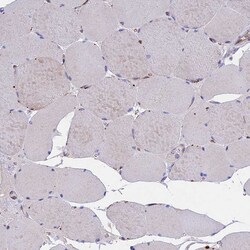

Immunogen sequence: KRTAVRLGDP HFYQDSLWLR KEFMQVRR Highest antigen sequence identity to the following orthologs: Mouse - 96%, Rat - 96%.

| Antigen | TMEM138 |

| Anwendungen | Immunohistochemistry (Paraffin), Western Blot |

| Gen | TMEM138 |

| Gen-Alias | HSPC196; HSPC198; JBTS16; TMEM138; Transmembrane protein 138 |